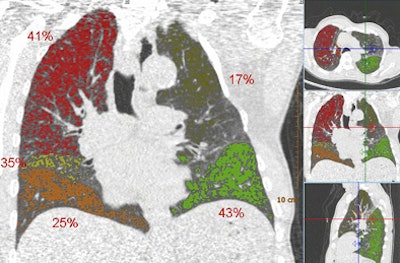

| Above, images from the expiration scan of a 65-year-old man with GOLD stage 3. The image shows increased density in some areas, common in expiration scans, but also regions that remain dark and are indicative of air trapping. Below, the overlay images from a single coronal section show that the left upper lobe is normal, while two lobes had emphysema and two had air trapping, indicating mixed-phenotype COPD. |